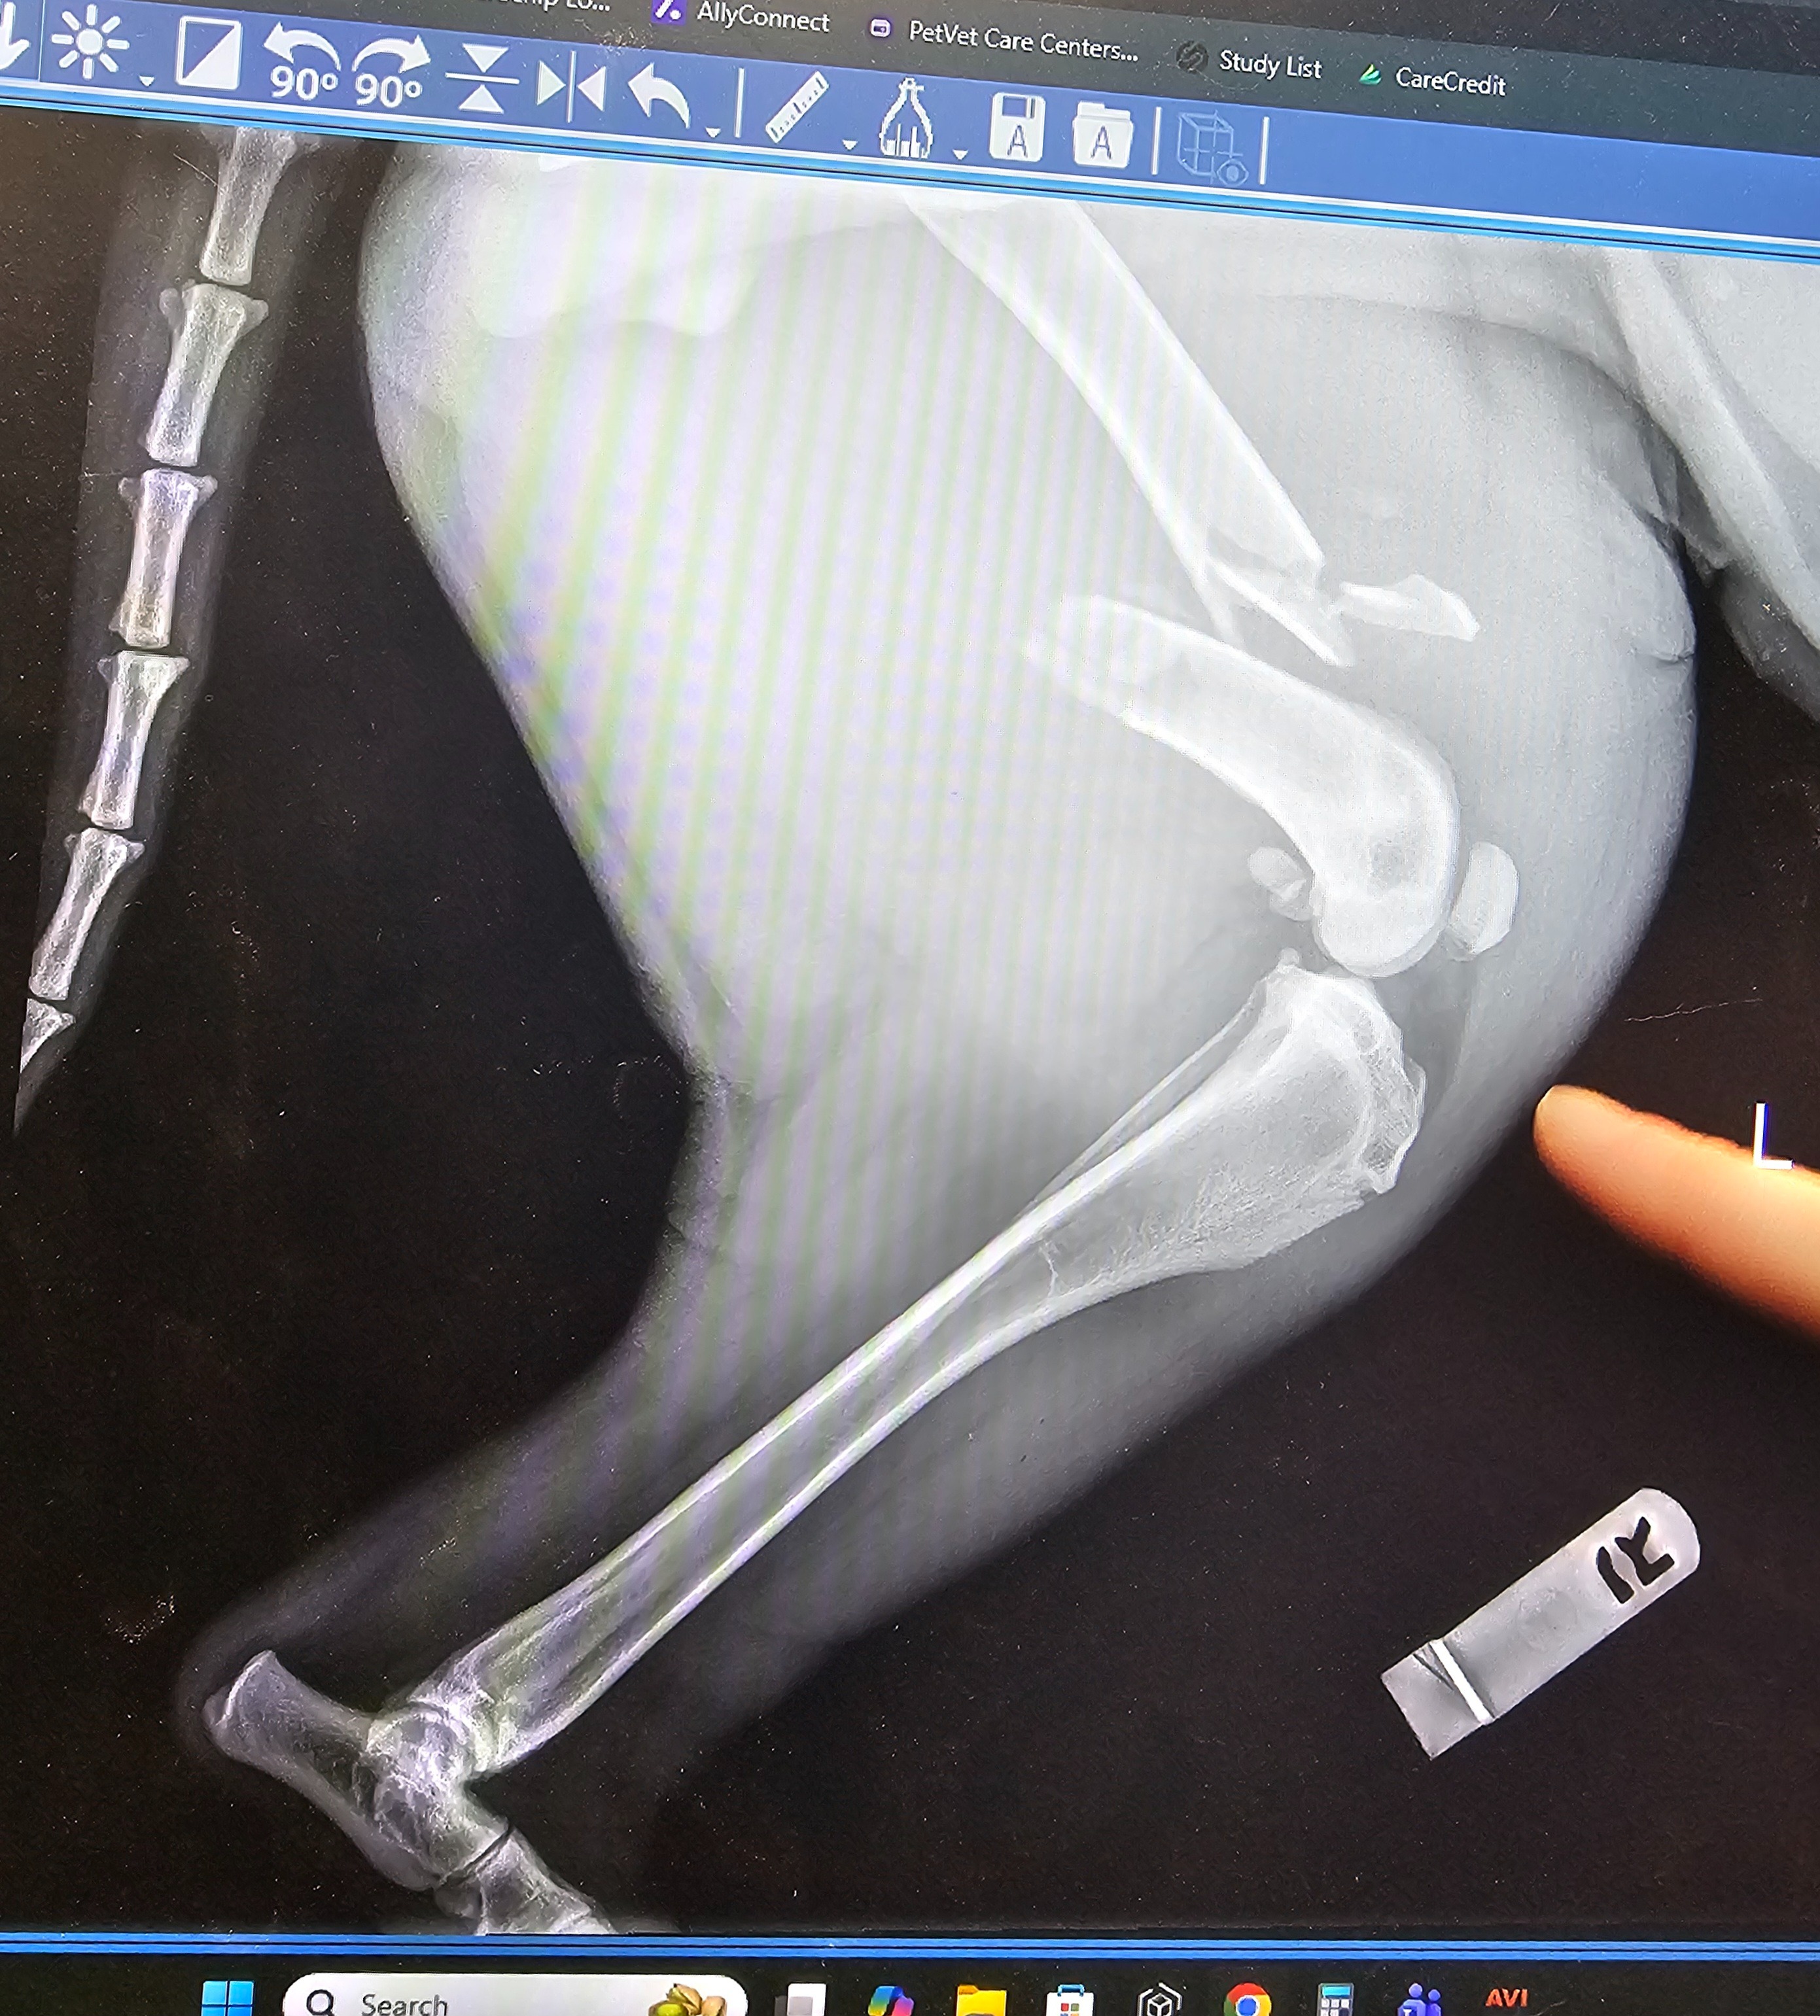

Our sweet girl, Mally Mae, had an accident on February 24th where she collided full speed with a chain link gate, resulting in her having a broken femur. The break is too high up for a standard splint, but the vet believes the leg can be saved by a specialty clinic with a surgical procedure involving plates. She is all set to have this operation take place on Monday, March 2nd at Blue Pearl in Olympia, but it is estimated to cost roughly $9,000.